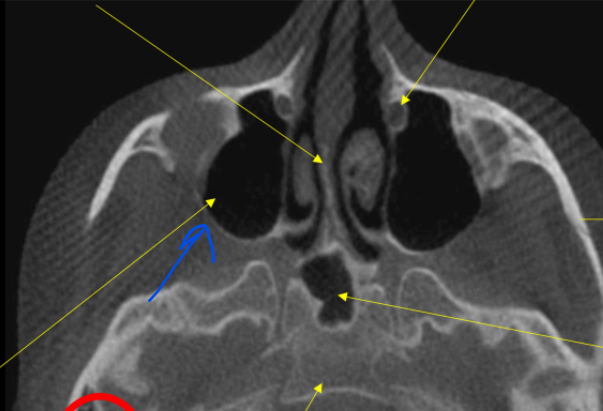

coronoid process

blue

what is this showing for the CBCT

volumetric rendering